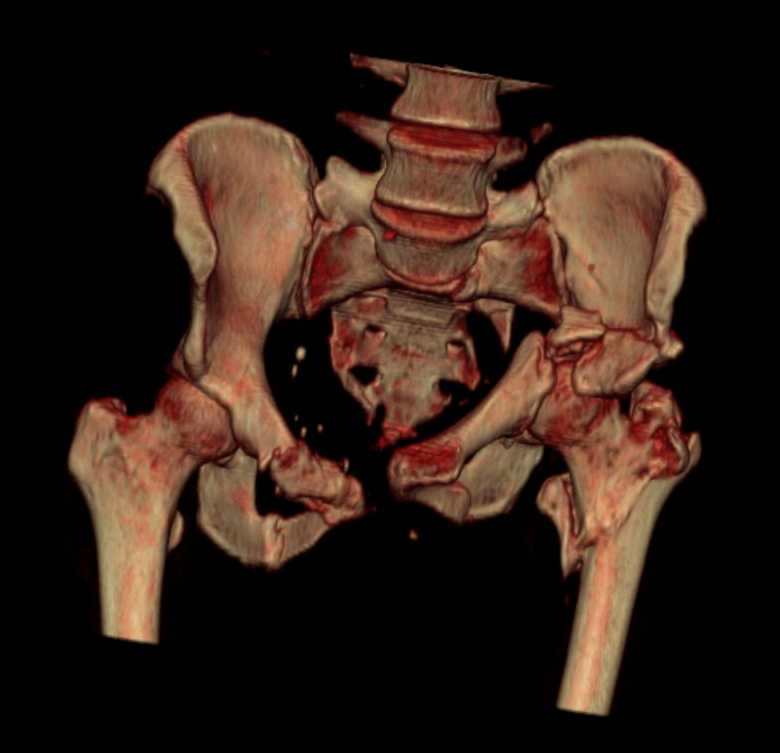

Больная 43 года (промышленный альпинист), 28.07.08 в результате падения с 5 этажа получила политравму:

Перелом свода и основания черепа. Вертикально-нестабильное повреждение таза, осложнённое разрывом мочевого пузыря. Чрезвертельный перелом левого бедра. Перелом правой таранной кости, переломовывих правой кубовидной кости. Тупая травма живота, разрыв печени, ушиб почек. Забрюшинная гематома. В день травмы - лапаротомия, ушивание ран печени. Разрыв мочевого пузыря не диагностирован. Течение болезни осложнилось развитием мочевого затёка и обширной пред- и забрюшинной флегмоны, сформировался свищ мочевого пузыря. 19.8.2008 вскрытие, дренировние флегмоны, ревизия мочевого пузыря, обтурация мочевого свища (свищ закрылся в октябре), 1.10.2008 некрэктомия, пластика по Шеде-Лидскому правой кубовидной кости. По результатам КТ диагностирован рак правой почки (диагностическая находка), 8.10.2008 нефрэктомия справа.

Переломы велись консервативно.

Имеется вертикальное смещение левой половины таза с выраженным отведением крыла (клинически подвижности нет), несросшийся низкий двухколонный перелом левой вертлужной впадины с потерей конгруэнтности, укорочение около5 см, застарелый разрыв лонного сочленения, неправильно сросшиеся переломы обеих ветвей правой лонной кости с укорочением, патологическая подвижность лоно-седалищного фрагмента слева. Правая нижняя конечность неопорна, несмотря на то, что лежа прямую ногу поднимает, ходит на левой ноге (ортопедическая обувь) с костылями, справа тазобедренный ортез. Седалищные нервы работают.Урологи отпустили больную на 6 мес.